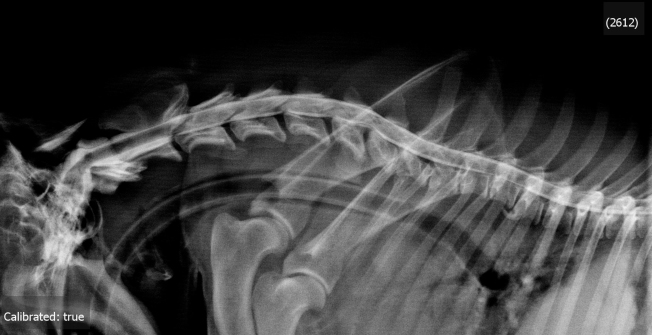

RADIOLOGIE : (ci-contre)

• sans préparation :

rachis cervical

• myélographie haute : injection cisternale de 4 ml d’Ioméron 350mg radiographies neutres et dynamiques (hyperflexion / hyperextension)

• l’examen clinique et radiologique est en faveur d’un Wobbler syndrome à composante dynamique et statique avec anomalie morphologique de C7 et hernie protrusive C5C6 et C6C7

• une décompression chirurgicale C5C6 et C6C7 est indiquée

•  une stabilisation C6C7 est impérative

• contrôle radiologique (ci-contre)

Conclusion : ré-alignement du canal médullaire en C6C7 et maintien espace intervertébral C6C7 physiologique

Position neutre

Hyperflexion (dédoublement ligne contraste en C6C7)

CCL : discopathie C6C7 avec anomalie morphologique C7 «tiping»

CCL : compression médullaire C5C6 et surtout C6C7 latéralisée à gauche, majorée de façon dynamique à l’hyperextension et minorée à l’hyperflexion en C6C7